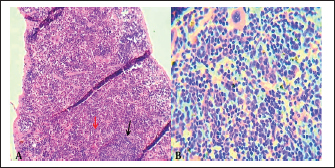

The microscopic examination of the liver and spleen sections revealed moderate to severe pathologic changes compared with the normal histological view of the sections from the control group. The histopathological figure of the infected liver showed hepatitis with multiple necrosis of hepatocytes and marked aggregation of the mononuclear leukocytes, periportal aggregation of leukocytes, with dilation of portal veins (Fig. 5). Histopathology of infected liver reveals chlamydial inclusion bodies (IB) within the cytoplasm of macrophages, as shown in Figures 68.

Fig. 5. A). Section of liver (Control) shows a normal central vein (V), a normal hepatic cords (h). H&E.100x. B). Section of liver (infected) shows hepatitis with multiple necroses (black arrows), periportal aggregation of leukocytes with dilation of portal veins (red arrow). H&E.100x.

Fig. 6. Section of infected liver with C. psittaci shows marked aggregation of the mononuclear leukocytes with chlamydial reticulate inclusion bodies (IB) within the cytoplasm of macrophages (Arrow), H&E stain, 400x.

Fig. 7. A). Section of chlamydial-infected liver shows chlamydial reticulate inclusion bodies (IB) within the cytoplasm of hepatocytes (Arrow), H&E stain, 400x. B). Section of infected liver shows inclusion bodies (IB) stained purple within the cytoplasm of macrophages (Arrows) with periportal aggregation of leukocytes and dilation of portal veins, Giemsa stain, 400x.

Fig. 8. Section of liver (infected) shows chlamydial inclusion bodies (IB) within the cytoplasm of macrophages (Arrows), 400x, A). Giemsa stain, B). Gimenez stain.